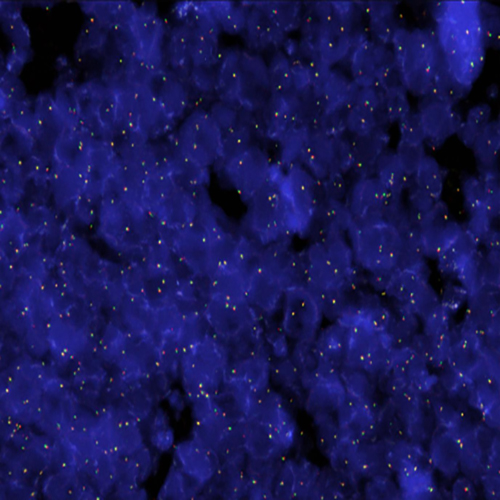

FGFR1 (8p11) Break probe hybridization to a tissue section showing a normal pattern.

FGFR1 has been implicated in the tumorigenesis of haematological malignancies, where it is frequently involved in balanced chromosomal translocations, including cases of chronic myeloid leukemia (BCR-FGFR1 fusion) and the 8p11 myeloproliferative syndrome/stem cell leukemia-lymphoma syndrome, which is characterized by myeloid hyperplasia and non-Hodgkin's lymphoma with chromosomal translocations fusing several genes, the most common being a fusion between ZNF198 and FGFR1. The FGFR1 (8p11) Break FISH probe is optimized to detect translocations involving the FGFR1 gene region at 8p11 in a dual-color assay on FFPE tissue sections.